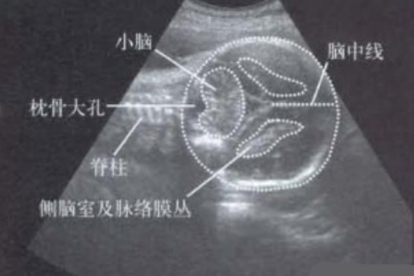

小脑延髓池增宽的原因有哪些

小脑延髓池增宽可能由遗传因素、脑脊液循环障碍、颅内感染、颅脑外伤、先天性发育异常等原因引起。小脑延髓池增宽通常表现为头痛、呕吐、步态不稳等症状,需通过影像学检查确诊。

5、先天性发育异常

小脑扁桃体下疝畸形、颅底凹陷症等先天性疾病可直接导致小脑延髓池结构异常。这类患者可能伴随共济失调、吞咽困难等症状。轻症可观察随访,严重者需行后颅窝减压术,术后可配合甲钴胺片营养神经。